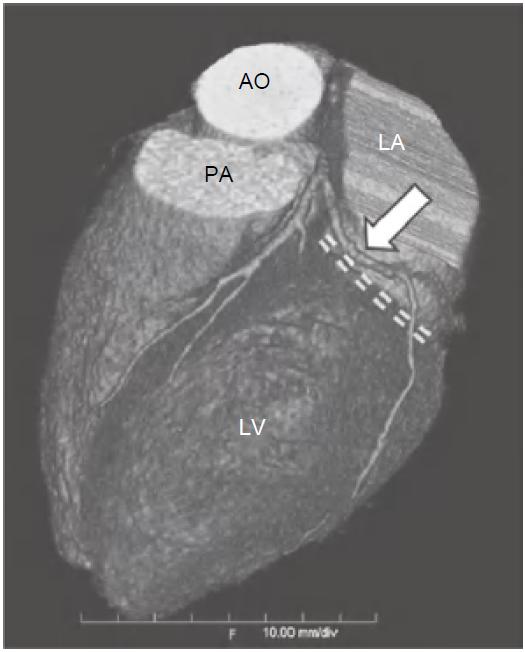

图13-2 左旋支(箭)起自左主干分叉处,并沿LAVG(虚线)走行,为左心室侧壁供血

AO.主动脉;PA.肺动脉;RV.右心室;LV.左心室